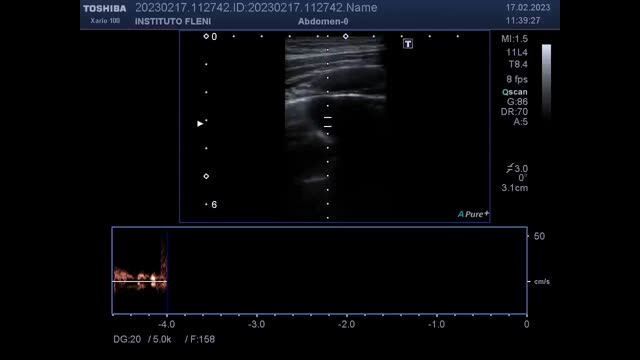

A-33-year-old man, with family history of Rendu–Osler–Weber syndrome, presented with seizures. Brain tomography showed a parietal brain lesion, and chest tomography reported a hyperdense nodular image in the right middle lobe. Lung point of care ultrasound (POCUS) was performed, and a round hypoechoic image with anterograde and retrograde flows was shown (Fig. 1), which moved with the ventilatory pattern. CT pulmonary scan revealed a dilated vascular structure in a coiled arrangement in the right middle lobe with multiple pulmonary arterial branches directly communicating with the pulmonary veins, compatible with complex pulmonary arteriovenous malformation (PAVM). Brain biopsy revealed a brain abscess, so antibiotics were started. Later, he was referred for angioembolisation.

Lung CT revealed a dilated vascular structure in the right middle lobe close to the pleura (A and B, white arrow), compatible with PAVM. Pulmonary echography showed a right parasternal hypoechoic image with an intraluminal hyperechoic area, compatible with thrombosis (C, white arrow). Doppler mode revealed a ‘mosaic-pattern’ indicative of mixing of arterial and venous blood consistent with PAVMs (D). Here, the anterograde and retrograde flow form a “ying-yang sign” (asterisk). Pulsed doppler image demonstrated arterial and venous flows (E).

PAVMs are rare, abnormal low resistance vascular structures that connect a pulmonary artery to a pulmonary vein, resulting in an intrapulmonary right-to-left shunt. The preferred screening test for PAVM is transthoracic contrast echocardiography, while thin section CT scanning is the imaging of choice to diagnose a PAVM.1 However, under certain circumstances, lung POCUS can demonstrate PAVMs. Pulmonary ultrasound perform with a good acoustic window can detect vascular malformations close to pleura, or only partially embedding the parenchyma.2 POCUS is a useful tool to rule out differential diagnosis of pulmonary images.